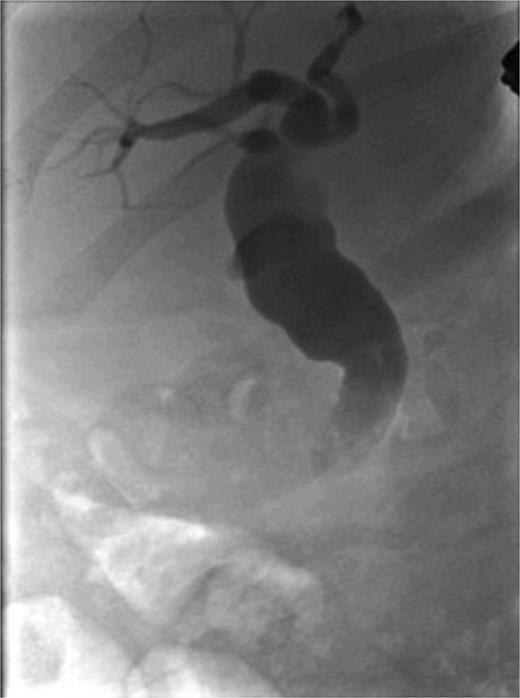

Following a brief clinical response to the initial conservative management for 24 hours, the patient started deteriorating and developed generalized peritonitis with worsening of inflammatory markers (C-reactive protein escalated to 438 mg/l). Consequently, she underwent an emergency diagnostic laparoscopy as the cause of peritonitis was not clear. Intraoperatively, it was observed that there was free bile in the peritoneal cavity, more so around the liver and the right paracolic gutter. There was also a bile collection behind the right colon and hepatic flexure of the colon, raising the possibility of a retroperitoneal source. The hepatic flexure of the colon was mobilized to assess the source of the leak. No obvious ongoing leak was noticed. As a precautionary measure, an Upper GI endoscopy was conducted intra-operatively to rule out any gastroduodenal perforation, as no obvious source of bile leak was seen from the biliary tree. This revealed the presence of bile in the stomach and confirmed normal anatomy up to the third part of the duodenum. The remaining intra-abdominal organs appeared unremarkable. Thorough peritoneal lavage was given, and 22 Fr abdominal drains were placed in the subhepatic, para-hepatic space, and pelvis, respectively, as the source of leak was not found. The following day, an endoscopic retrograde cholangiopancreatography (ERCP) was performed, which identified a small leak around the area of the cystic duct stump (Fig. 3). In response, a 5 cm-sized 7 Fr double pigtail stent was inserted into the CBD. A post-ERCP CT scan was performed to evaluate the contrast leak. The CT imaging revealed an extraluminal contrast leak originating from a defect in the posterior CBD (Fig. 4). Notably, the cystic duct stump remained intact and anterior, establishing the diagnosis of Spontaneous biliary leak from the CBD.

Axial and coronal section CT imaging revealing contrast leak from the bile duct; a) Contrast leak from the posterior aspect of CBD (arrow). b) Contrast extravasation into the subhepatic drain (arrow).